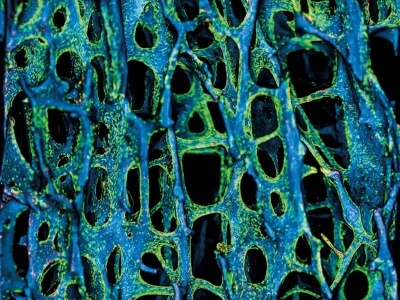

СОСТАВ.

Высокоочищенный ксено-коллаген I-го и III-го типа крупного рогатого скота, полученный по технологии «ОСТЕОМАТРИКС», в результате многоэтапного процесса очистки, химической обработки с соблюдением самых жестких норм безопасности.

Мембрана и флис 3D «БИОМАТРИКС» имеют двухслойную структуру.

Флис 3D отличается от мембраны более выраженной пористой структурой и повышенной гидрофильностью.

Плотный слой одинаков в обеих формах.

СВОЙСТВА.

Материал обладает высокой биосовместимостью с мягкими тканями и низкой антигенностью - не иммуногенен. Это позволяет использовать его в качестве покрытия раневых поверхностей и внесенных материалов для изоляции от воздействия факторов внешней среды и вероятности вторичного инфицирования.

Материал гидрофилен.

Пористый слой (мягкий) представляет собой «губку», структуру с повышенными гидрофильными (удержание жидкости: кровь, антибиотики и т.п.) и пониженными компрессионными (давление по площади) свойствами.

Плотный слой препятствует прорастанию быстрорастущих клеток мягких тканей и надёжно изолирует от воздействия факторов внешней среды.

Возможна фиксация на месте с помощью шовного материала, пинов и т.п.

Материал резорбируется в течении нескольких недель.

Поскольку ксено-коллаген имеет природное происхождение, в сухом состоянии мембрана и флис 3D «БИОМАТРИКС» может иметь незначительные деформации и различную толщину.

Продукты биодеградации (лизиса) стимулируют заживление раны, значительно увеличивая толщину и качество мягких тканей.